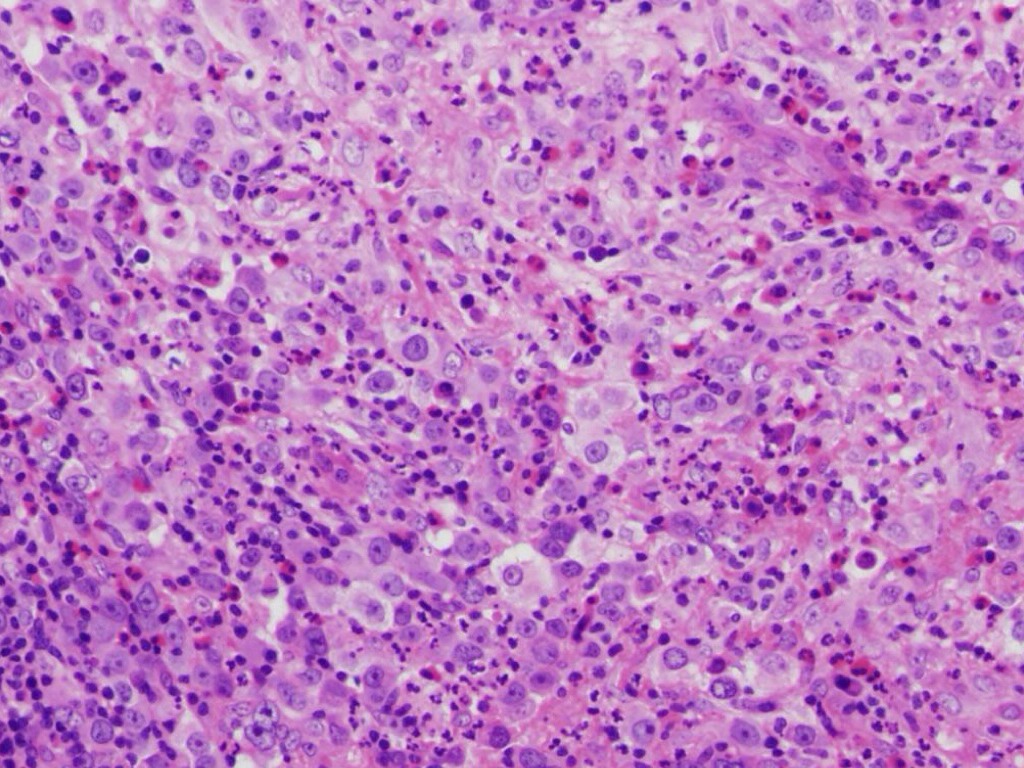

CM

• Mezcla de células de Reed-Sternberg con células no neoplásicas

• Neutrófilos

• Histiocitos

• Células plasmáticas

• Eosinófilos y linfocitos

Untitled Slide